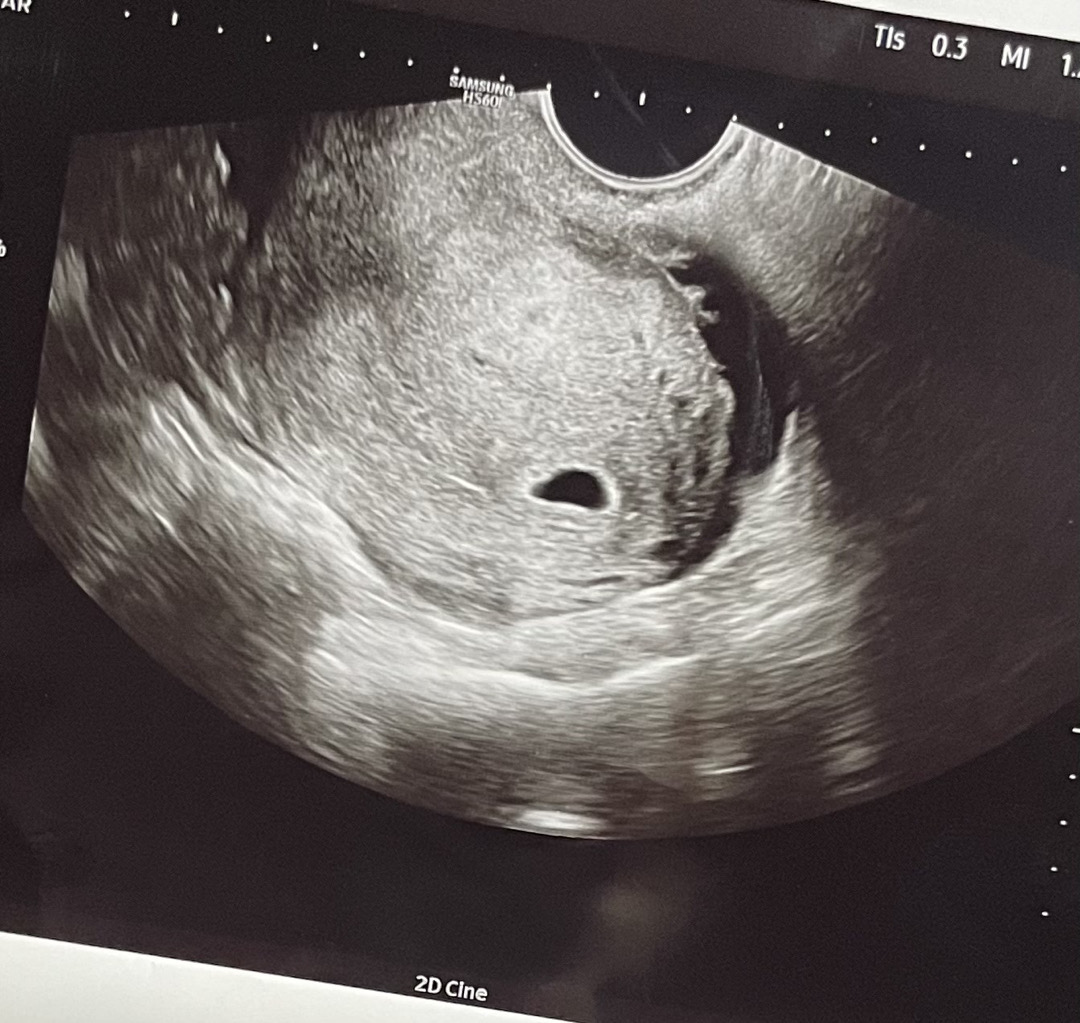

아기집 모양 어떤가요?ㅠㅠ

조금 찌그러진것 같아서 걱정돼요 4주6일이구..몇달전에 계류유산하고 찾아온 아기에요…

모양 예쁘게 부풀은 호빵같구 예쁜데요?ㅎㅎ 저는 찌그러진 길쭉한 오이모양이에여ㅎㅎ 처음에 왜 모양이 이상할까 했는데, 연연하지 않기로 했어요.. 지금은 잘 붙어있어줘서 고마울 뿐이에요 ㅎㅎ